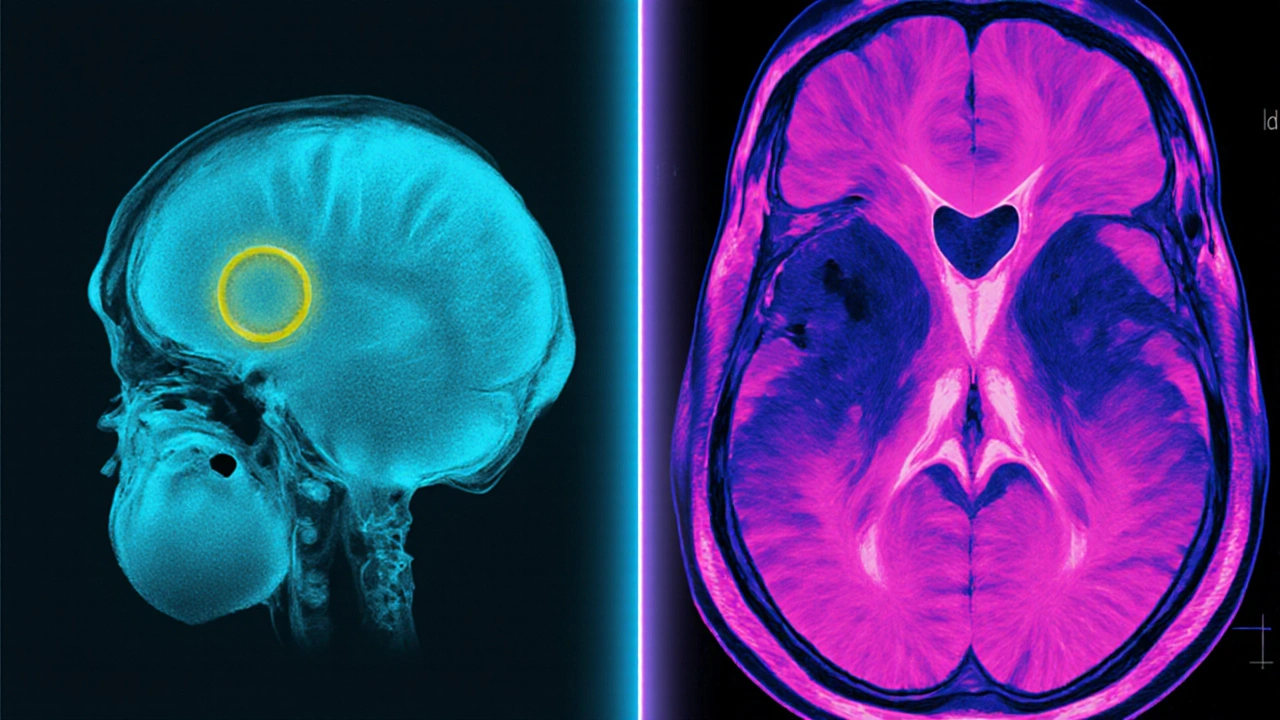

When Ultrasound Isn’t Enough - The Role of Fetal MRI

In about 10‑15% of cases, the ultrasound image is limited by fetal position, maternal habitus, or low‑grade acoustic windows. That’s where fetal magnetic resonance imaging (MRI) a high‑resolution imaging technique that uses magnetic fields to capture detailed anatomy without ionizing radiation

MRI excels at delineating the spinal cord, level of the defect, and associated brain malformations such as ventriculomegaly. It also helps the multidisciplinary team decide whether in‑utero repair is feasible.

Typical MRI protocol includes T2‑weighted single‑shot fast spin‑echo sequences in three orthogonal planes. The exam takes about 30‑45 minutes and can be performed safely after the 20‑week gestation mark.